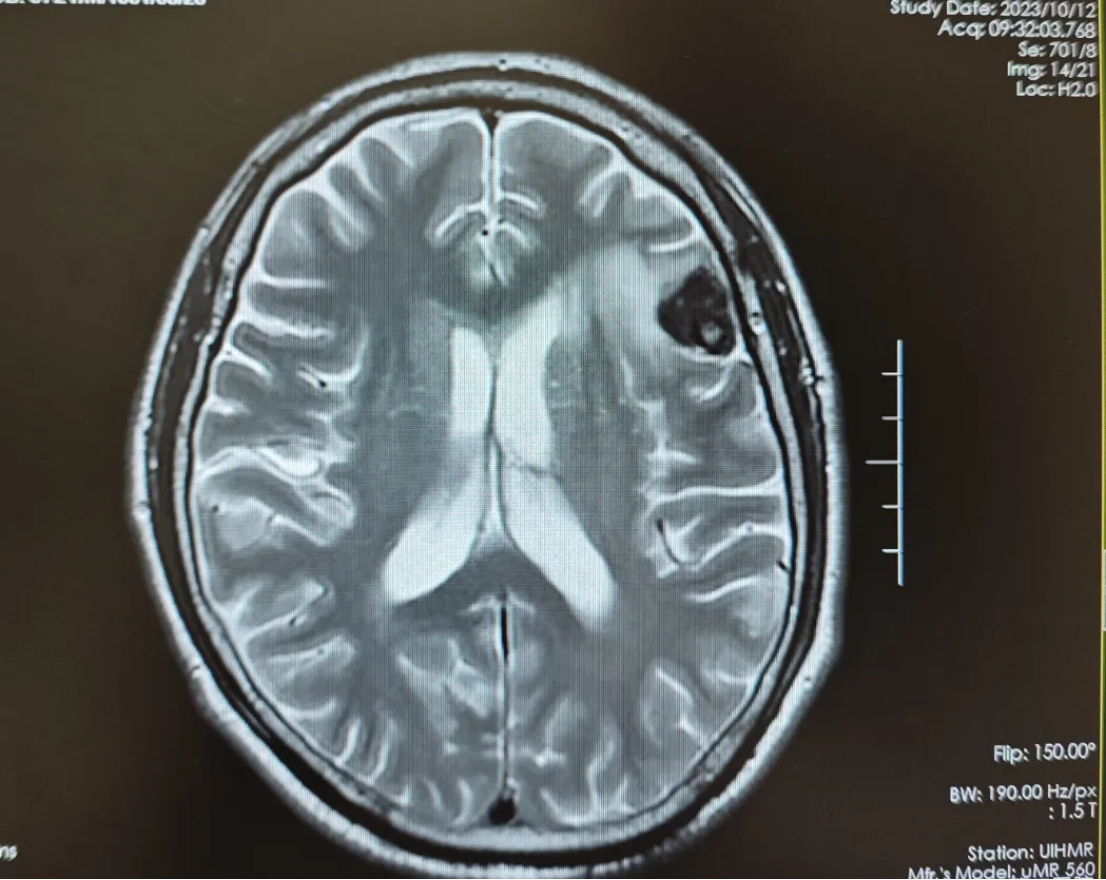

开始给予恩沃利单抗200mg d1、8+伊立替康100mg d1、8+替尼泊苷50mg d1,2,8,9方案化疗,过程顺利。2023-10-12化疗2周期,复查头颅磁共振平扫提示,左侧额叶占位性病变,大小约1.7cm*1.7cm,较前片(2023-08-15)病灶及周围水肿明显缩小;脑内多发缺血腔梗灶;老年性脑改变(图2)。2023-11-08替尼泊苷末次治疗,患者情况稳定,主观评价良好,实现PR。

图2 化疗2周期复查头颅磁共振平扫